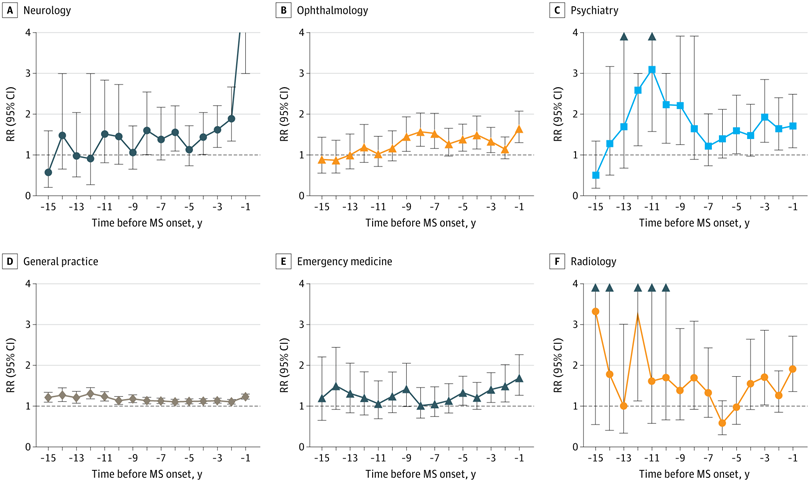

【MSの症状が現れる最大15年前から、どの診療科をどれだけ頻繁に受診していたかの表(対照群と比べた相対的な頻度)】

Health Care Use Before Multiple Sclerosis Symptom Onsetより X軸:MSの発症前の年数(−15年〜−1年)

Y軸:受診の相対リスク(Rate Ratio:RR)。1.0より高ければMS患者群の方が多く受診していたことを意味する

【表からの読み取れること】

・精神疾患(抑うつ・神経症):発症の4〜5年前から増加(RR最大2.34)

・めまい・不眠など:発症の2年前から有意に増加(RR最大1.99)

・視覚障害:発症前年にRR 3.47と高く、他にも視力調整異常や眼球運動障害も増加

・筋骨格系(関節症・膝の異常):発症前年にRRが上昇(RR最大1.95)

【表のまとめ】

・多発性硬化症の診断前に患者が特定の診療科をより多く受診していることを示している

・特に、精神科・神経科・眼科・救急・放射線科の受診が数年前から増加しており、MSの早期兆候を捉える重要な手がかりになる可能性がある

・発症の10年以上前から変化が始まっている場合も示唆されている

また、MS患者においては、診断の約8〜9年前から神経内科や眼科への受診回数が急増し、診断直前になると身体的な症状による通院が一気に増えるという明確なパターンも浮かび上がりました。